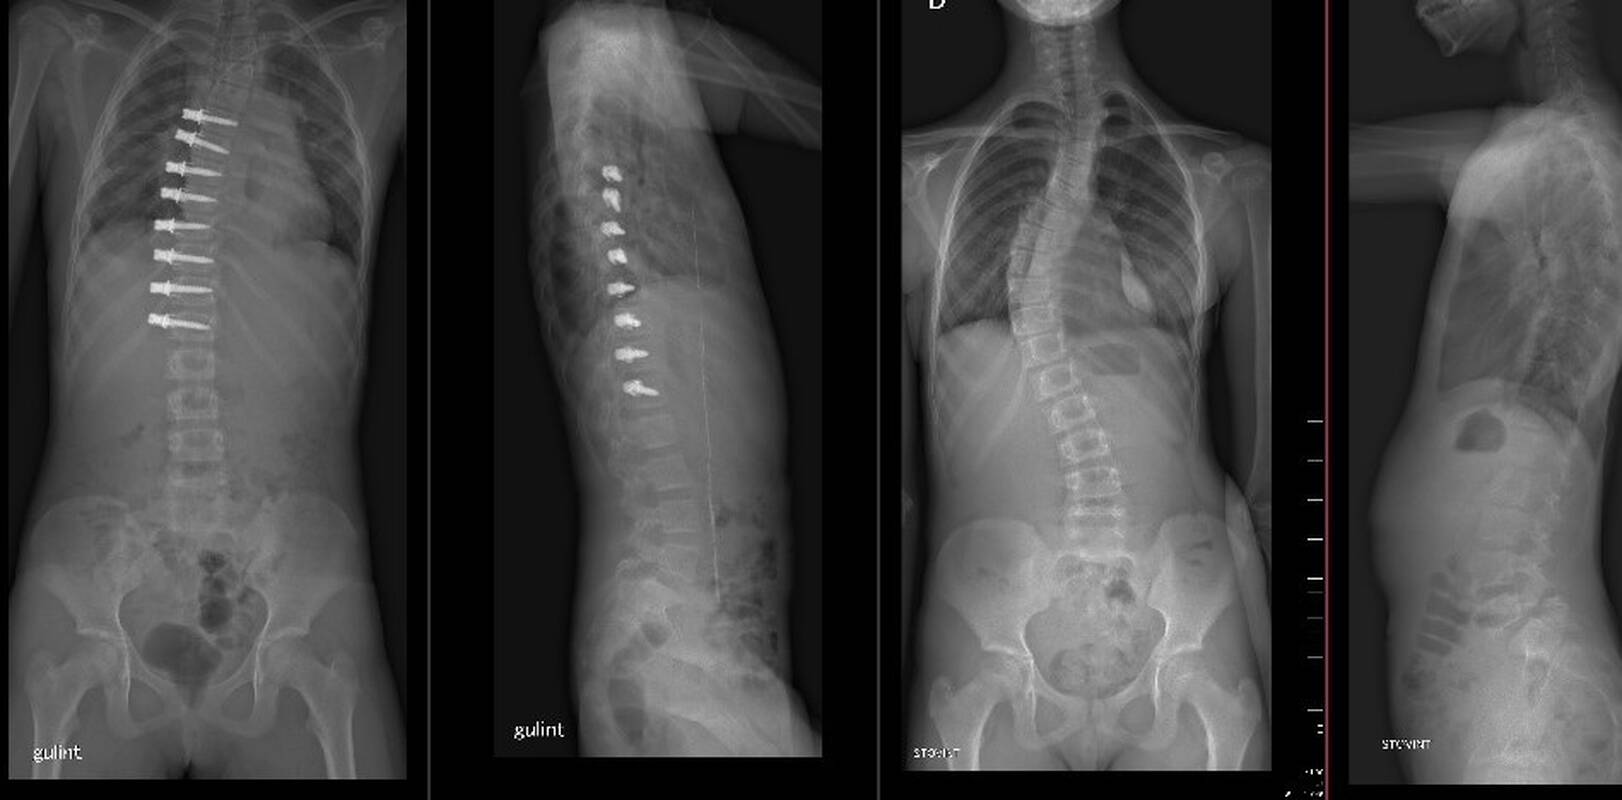

Atliekant šią inovatyvią operaciją, gydytojus ortopedus-traumatologus stebėjo ir konsultavo stuburo deformacijų operacijų žinovas prof. Ilkka Helenius iš Suomijos. Mažai invazyvi operacija buvo atlikta iš šono per nedidelius pjūvius, o į stuburo slankstelių kūnus įsriegti titaniniai sraigtai sutvirtinti specialia lavsanine juosta. Būtent ji lemia, kad augančio vaiko stuburo slankstelių mobilumas nenukenčia.

Kaip teigia jau ne vieną inovatyvią stuburo operaciją vaikams atlikęs gydytojas ortopedas-traumatologas dr. G. Bernotavičius, pritaikius šią operacijos techniką, stuburui augant, iškrypusi jo pusė bus stabdoma, o kita pusė augs ir stuburas tiesinsis, neprarasdamas savo prigimtinio lankstumo.

Šiai operacijai atlikti buvo pasirinktas intensyviai augantis dvylikos metų vaikas, kurį gydytojai stebėjo jau ketverius-penkerius metus, ir kurio skoliozė siekė 50 laipsnių ir vis dar progresavo.